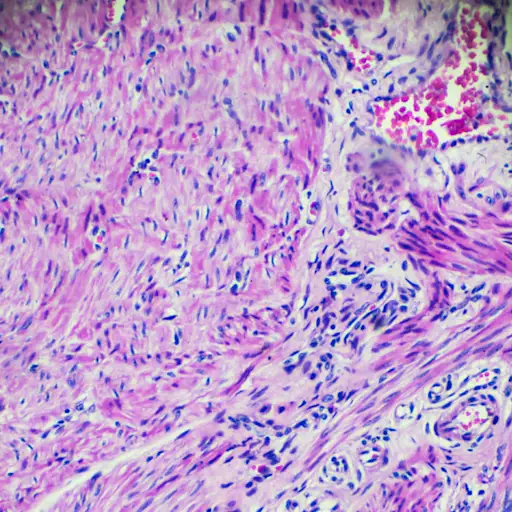

例如,在梅奥,例如,审查患者患者的患者肿瘤牌一群妇科肿瘤学家、病理学家、放射科医生和其他专家,他们审查所有病人的玻片,寻找微转移(通过淋巴血管系统扩散的癌细胞群)。如果有人发现更多的癌细胞群,那么癌症将被视为第三阶段,这意味着患者将接受化疗和放射治疗。